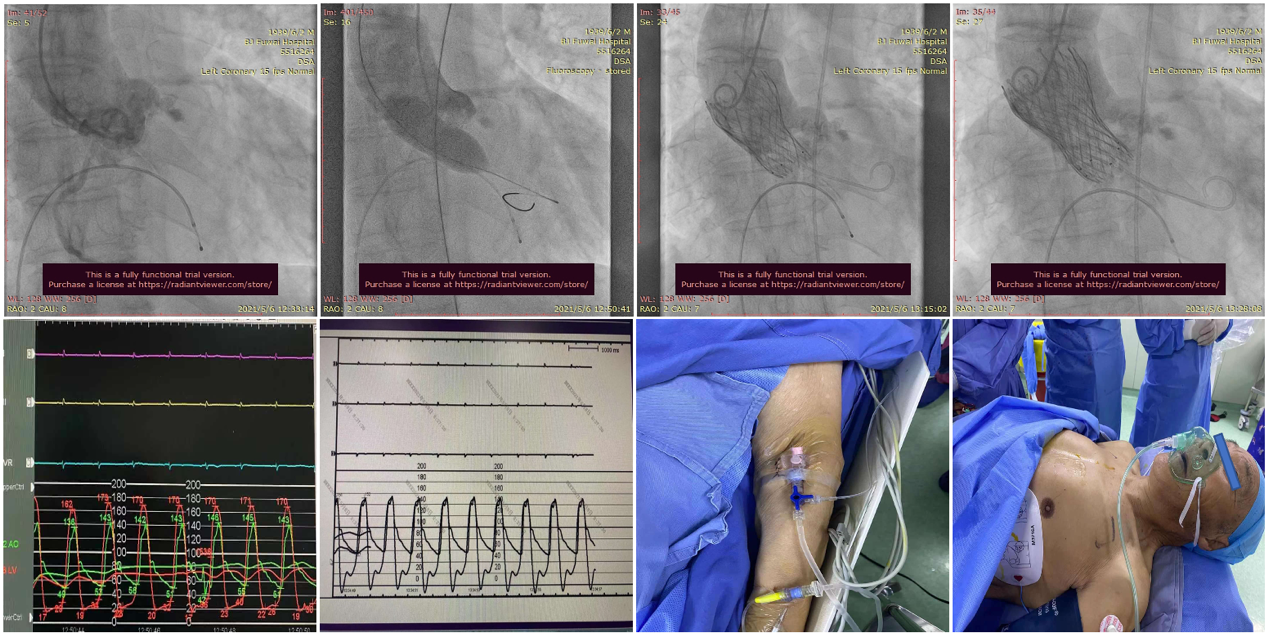

手术当天,病房护士提前行左肘正中静脉留置针作为补充液体通路;患者送达介入导管室后,省去经颈内静脉穿刺行中心静脉置管、经食道超声检查、术前导尿和麻醉师全身麻醉及气管插管或喉罩通气等过程;患者经过消毒及铺单后。半支(50mg)利多卡因局部麻醉后,穿刺右桡动脉作为辅入路,立即检测动脉血压;四支(400mg)利多卡因局部麻醉后,血管超声引导精准穿刺右股总动脉,两把ProGlide预埋处理后,作为主入路,置入20F 长导引鞘管(戈尔公司),立即动脉给予肝素5000单位;经右股静脉入路,将漂浮电极送入右心室心尖,临时起搏器调整至120次/分调试及测试患者的耐受性。主入路和静脉起搏器入路建立过程中,密切关注患者的血压心率等生命体征无明显异常,患者无明显不适。经右桡动脉送角度猪尾于右冠窦,采用右窦中心投照体位(右2°,足8°)行主动脉根部造影;

AL2导管配合直头超滑导丝进行跨瓣;

交换为头端塑形好的Landerquist超硬导丝,采用23 mm NUMED-II球囊对狭窄钙化的主动脉瓣进行预扩张,同时造影显示球囊完全封闭主动脉瓣,几乎无反流;

根据瓣上结构测量及球囊预扩张效果,采取“Down-size”策略,选择A-26 Venus A瓣膜,通过输送系统完成过弓和跨瓣;Venus A瓣膜精准定位于瓣环水平,

在临时起搏器控制心室快速起搏下完成瓣膜释放;

由于本例患者原瓣叶融合钙化较重,采用“瓣中瓣”技术植入另外一个A-26 Venus A瓣膜,

采用23mm NUMED-II球囊对植入的瓣膜进行后扩张;

最后造影显示新植入的瓣膜位置理想,少量瓣周反流,

跨瓣压差由术前30 mmHg下降至4 mmHg;即刻经胸超声评估主动脉瓣位植入生物瓣峰值流速为2.0 m/s,平均跨瓣压差为16 mmHg,少中量瓣周反流,左室射血分数为45%;评估患者心率为67次/分并且心电图较术前无明显异常,故即刻拔出临时起搏导线。整个手术过程仅采用局部麻醉,无任何镇静剂使用,患者全程清醒,配合良好,在球囊扩张主动脉瓣及瓣膜释放过程的血压及心率等生命体征与既往全麻相比无明显异常,患者略感心慌及无力。(图3)。术后患者平卧24 小时即下床活动,进行康复训练;采用阿司匹林100 mg (QD)和氯吡格雷75 mg(QD)行双联抗血小板治疗,术后4天顺利出院。

图3患者经导管主动脉瓣置换术及围术期操作

A:主动脉根部造影;B:23 mm球囊预扩张;C:26型号VenusA瓣膜植入;D:26型号VenusA“瓣中瓣”位置良好,少量瓣周漏;E和F:术前及术后经导管跨瓣压差;G:肘正中静脉留置针;H:患者全程清醒状态。